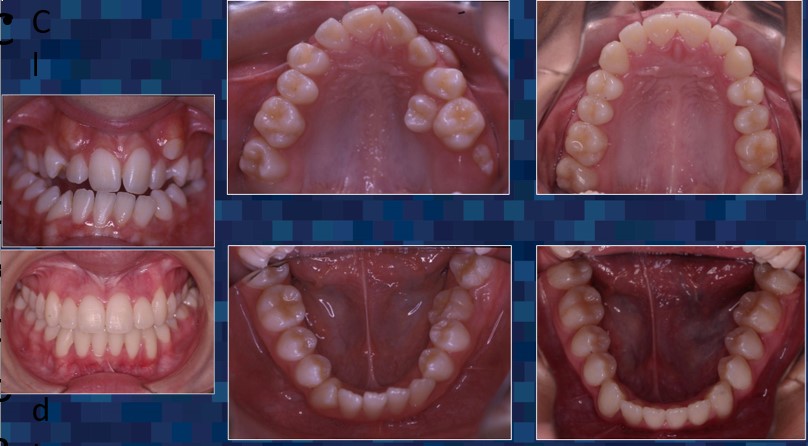

For over 30 years, Dr. Guerrero has made it his mission to improve the lives of his patients through specialized surgical care that restores function and comfort. Dr. Guerrero’s work embodies precision, compassion, and a dedication to patient well-being. Corrective jaw surgery is one of the advanced services offered, designed to address functional issues and enhance the quality of life for those who need realignment and reconstruction.